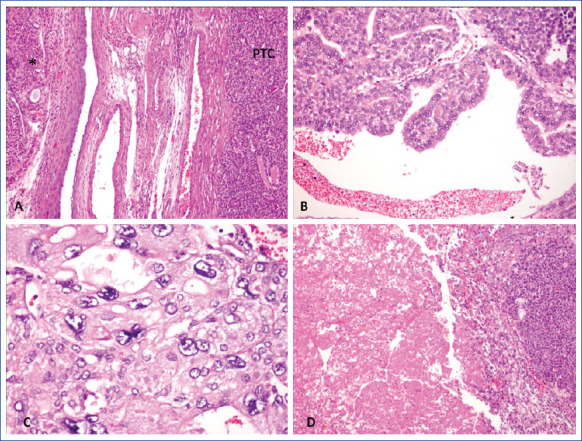

Abstract Image